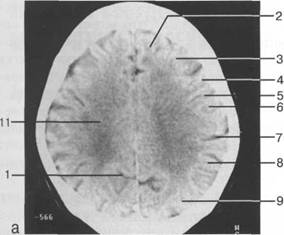

проведенной от наиболее дистальной точки затылочного рога к костям свода череп 13513u2010n 72;. Считает

теменно-затылочная борозда; 11 - семиовальные